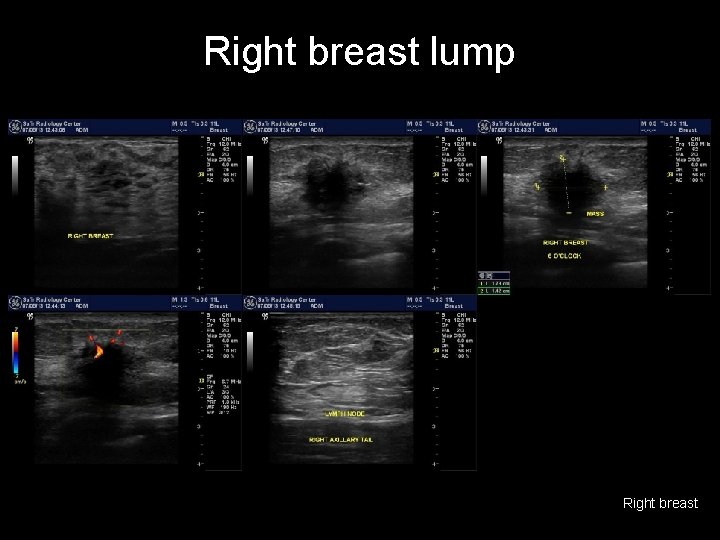

Right breast lump • Second study? – Ultrasound – Mammography – MRI w contrast

Right breast lump Right breast

Right breast lump • • irregular mass, hypoechoic, with heavy post acoustic shadowing and hypervascularity the lymph nodes appear reactionary with preserved sinus BREAST CANCER (BIRADS V) http: //radiopaedia. org/cases/breast-cancer-7